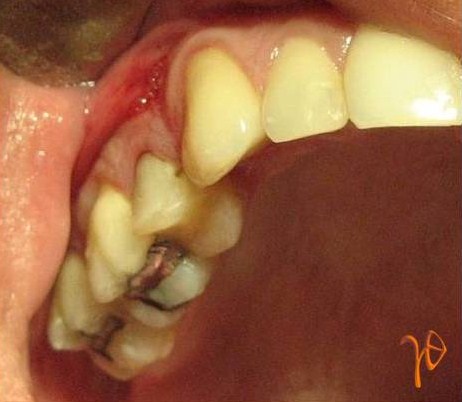

Εικ. 2: Κλινική εικόνα της Περίπτωσης-1

Ο 25-χρονος ασθενής παραπέμφθηκε για λοίμωξη στην πρόσθια περιοχή της άνω γνάθου(ΔΕ).